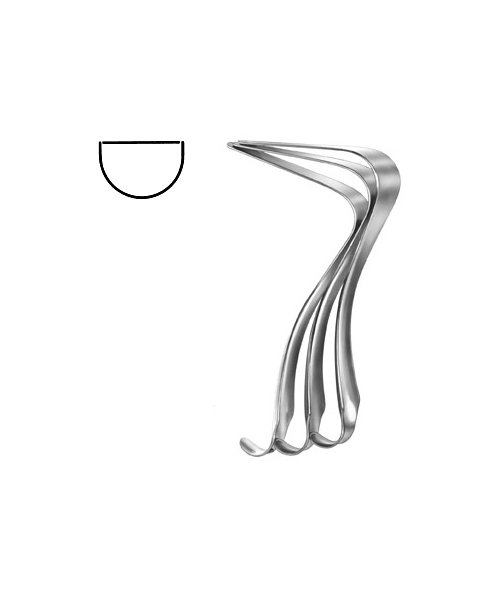

- Gynecology, Surgical Instruments

Endocervical Speculum

- Size : 34.5 CM - 13 1/2"

- Read more